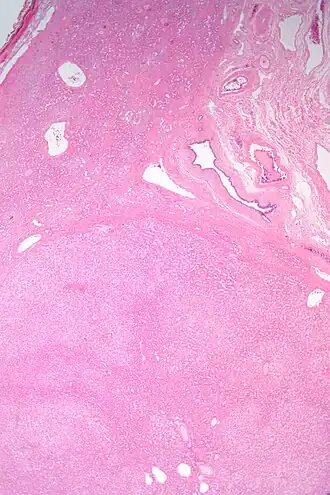

ГА обычно единична, но иногда встречаются множественные образования под названием «гепатоцеллюлярный аденоматоз». Размер варьируется от примерно 1 см (предел обнаружения для обычных методов визуализации) до более 20 см. Риск осложнений у пациентов с ГА менее 5 см практические отсутствует. В редких случаях и чаще у мужчин самые большие опухоли могут иметь злокачественные признаки. Гистологически клетки аденомы крупнее нормальных гепатоцитов, но не обнаруживают цитонуклеарной атипии. Портальных трактов, центральных вен или желчных протоков мало или их нет, но есть изолированные артерии. Клетки Купфера малочисленны или отсутствуют.